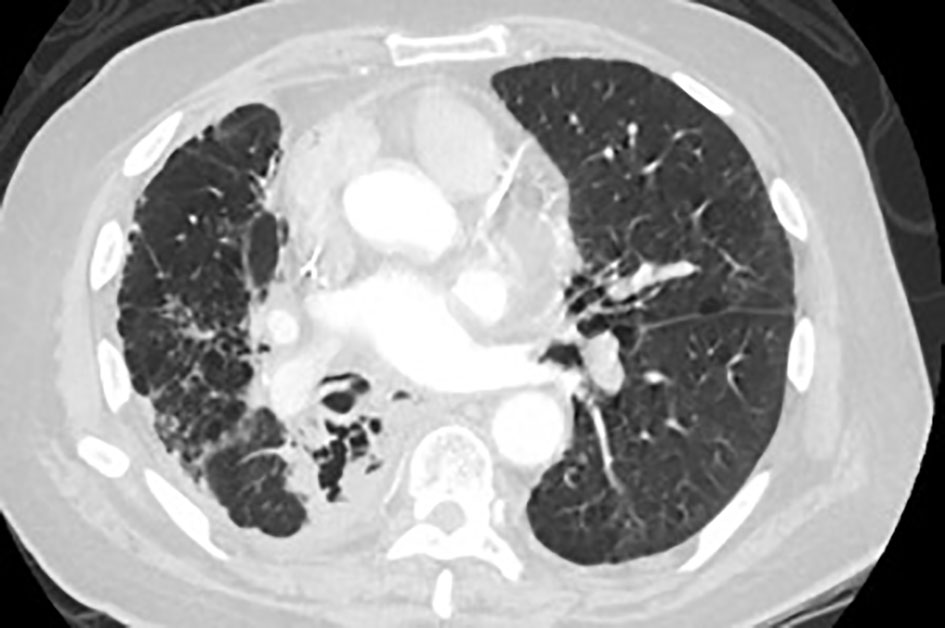

A 72-year-old male with past medical history of stage IV squamous lung cancer was brought to the hospital with complaints of anorexia, shortness of breath, and increased hemoptysis for preceding 4 weeks. His lung cancer was diagnosed 8 years earlier, when he presented with T4N2M0 non-small cell lung cancer treated with combined modality therapy consisting of chemotherapy and radiation to a dose of 6,480 cGy in 180 cGy fractions which led to a 7-year progression-free interval. One year earlier, he had recurrence of the cancer. Patient was not candidate for further radiation therapy. He received palliative chemotherapy with gemcitabine and carboplatin and after four cycles was placed on a chemotherapy holiday. Patient condition had been stable till 1 month prior to current admission when he developed progressive hemoptysis, right-sided chest pain and fatigue. On admission, chest X-ray (CXR) showed new worsened reticular markings along left lung base suggestive of infectious process. CT of chest showed findings consistent with interval progression of malignancy with an area of consolidation along the medial right lower lung (Fig. 1). Sputum culture showed mixed bacterial growth. Patient received short course of antibiotics followed by 10 fraction course of palliative radiation therapy. Immediately after completing his eighth cycle of radiotherapy, he developed progressive coughing and difficulty swallowing, together with shortness of breath, fever and confusion. He was readmitted, and CXR showed increased interstitial prominence at the bilateral lung bases. Laboratory workup revealed signs of infection with a WBC of 21.2 × 109/L. Procalcitonin was 0.12 ng/mL. He was diagnosed with hospital acquired pneumonia and received broad antibiotics coverage. His sputum culture revealed poly-microbial growth without organism identified. Due to concern of progressive coughing and difficulty swallowing a video, swallow evaluation was done. Surprisingly, it showed a TEF (Fig. 2) in the middle third of the esophagus. Patient underwent upper endoscopy and palliative esophageal stent placement (Fig. 3). Following successful stent placement, patient tolerated diet without complications. One week later, he was sent to hospice for further comfort measures.

![]() Click for large image | Figure 1. CT scan of the lung shows left apical necrotizing mass. |